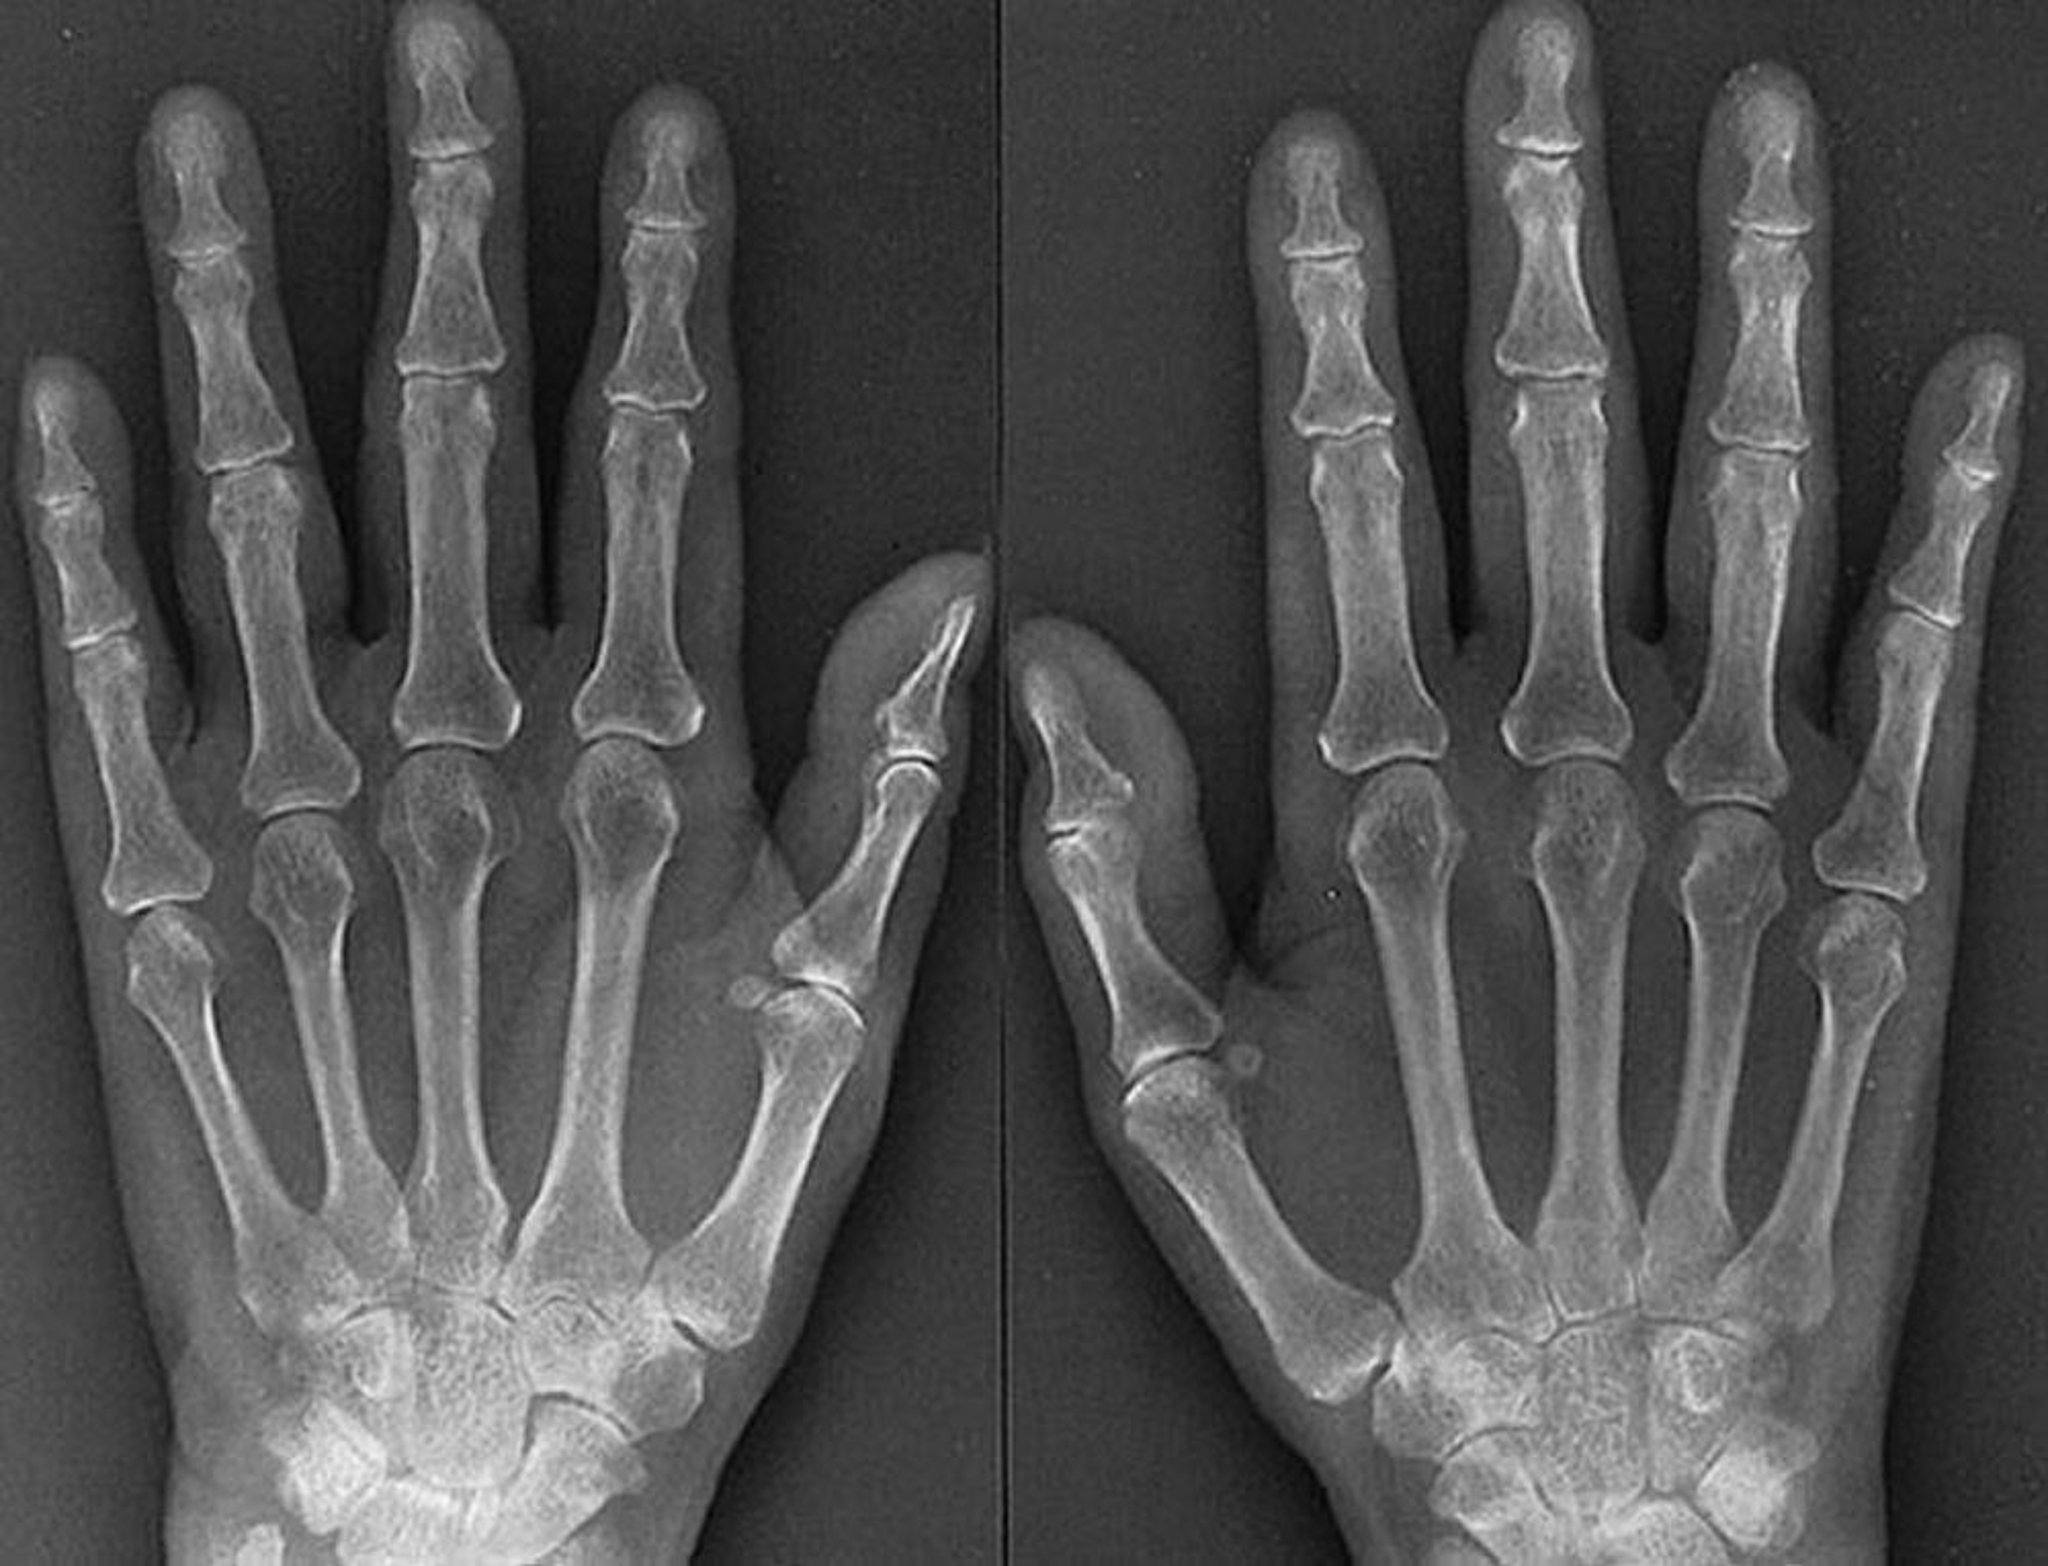

Características radiológicas de la artritis reumatoide temprana

Las características de la artritis reumatoide temprana agresiva, como se ve en esta radiografía de una mujer de 61 años con artritis reumatoide de 1 año de evolución, incluyen edema de tejidos blandos de las articulaciones metacarpofalángicas e interfalángicas proximales, osteoporosis periarticular, estrechamiento simétrico del espacio articular de varias articulaciones metacarpofalángicas e interfalángicas proximales de ambas manos, y erosiones sutiles de la tercera y la cuarta articulaciones metacarpofalángicasderechas y la cuarta articulación metacarpofalángica izquierda.

By permission of the publisher. From Matteson E, Mason T: Atlas of Rheumatology. Edited by G Hunder. Philadelphia, Current Medicine, 2005.